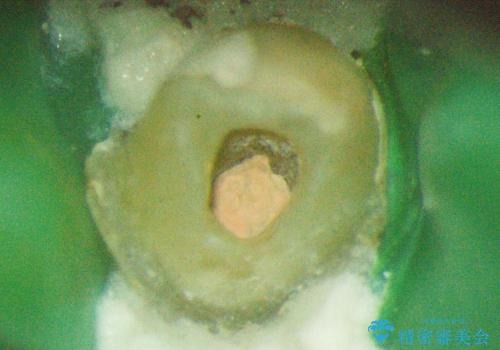

- 前歯の違和感を主訴にご来院された患者様です。

根尖性歯周炎に罹患し根の先に膿が溜まっているのが原因でした。

精密根管治療後、オールセラミッククラウンで治療を行いました。

精密根管治療では、菌を入れない環境を作り見逃しが無いようにマイクロスコープを使って治療する事が大切です。

まだ誰も触っていない根管ならばほとんどのケースで治せる事が出来ます。